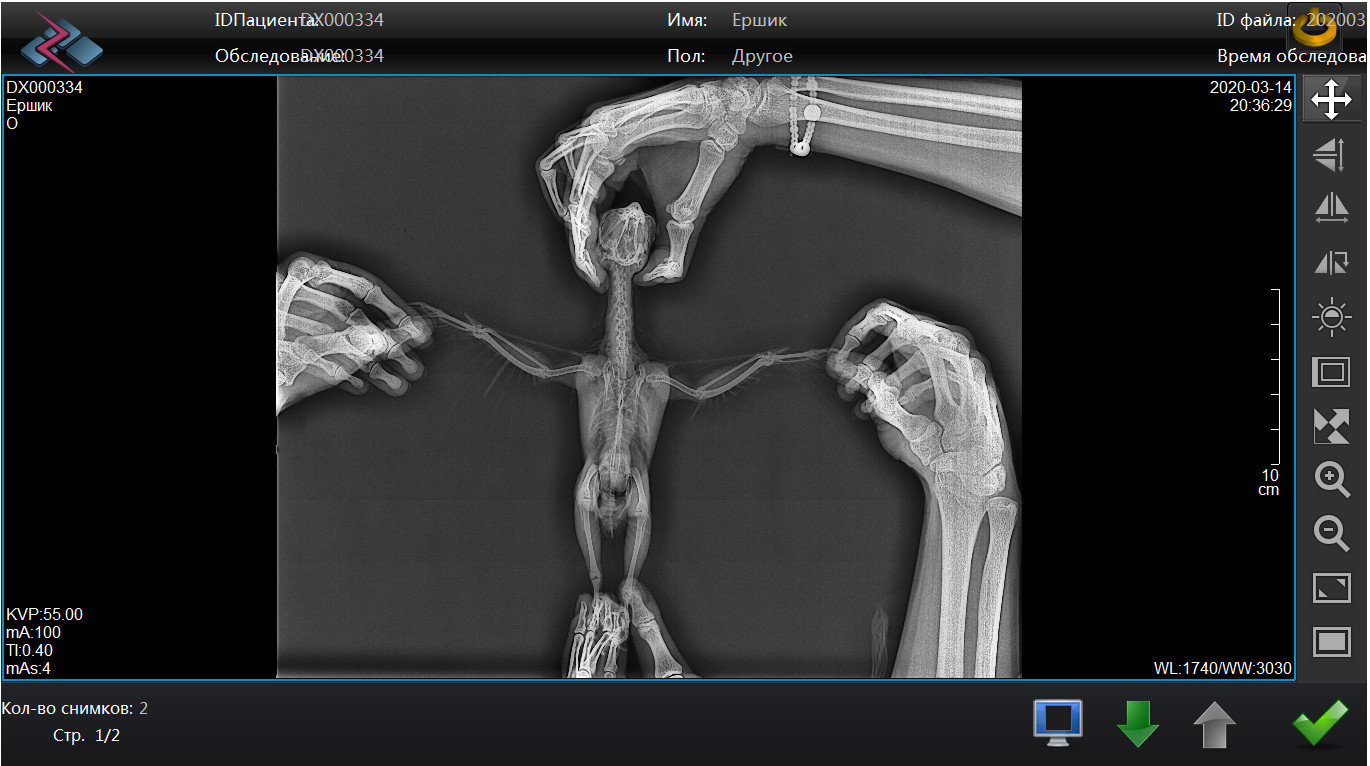

Pipka Опубликовано 18 апреля, 2020 Автор #73 Опубликовано 18 апреля, 2020 11.04.2020 в 21:10, Мария_К сказал: @Pipkaв надежде на хорошие новости от вас. @Мария_К , И ура!!!! Они таки хорошие!!!!!!! Люди, народ, поздравьте нас с Ёршиком!!!!!!! Мы поправились!!!! Не надо больше уколов, мерзких гадких заворачиваний в полотенце и принудительных выпаиваний горьким лекарством. МЫ ЗДОРОВЕНЬКИЕ!!!!! Посмотрите какой у нас чистенький и светленький рентгенччииккккк!!!!!!! Никаких затемнений, никаких гранулем или остаточных швов на легких. В сравнении с тем что было - день и ночь. Даже мне стало понятно и видно все. Мы поправились. По клинической картине: чихов нет, хрипов-сипов нет, нос чистейший, морду не трет, головой не дергает. Чуть позже выложу ввидео с ним. Пока вот рентген. Господи, как же я счастлива!!!!! Про липому все также. Без изменений. Но нам сказали что это фигня. Если будет правильно питаться и двигаться то больше чем есть не вырастет...

Pipka Опубликовано 18 апреля, 2020 Автор #74 Опубликовано 18 апреля, 2020 Извините, полосы - это мерцание на компе от телефона. Мне так не терпелось, что я прямо с компа на телефон щелкнула. а так ответ на диске, а у меня дома дисковода нема.

Pipka Опубликовано 18 апреля, 2020 Автор #75 Опубликовано 18 апреля, 2020 Мне все-таки кажется что главным в лечении был вариконазол. хотяя... может и байтрил и ингаляции свое дело сделали. Кстати, ингаляции я ему решила пока не отменять. пусть утром и вечером дышит хорошими парами полезными. Вместо курева того страшного. И элькар конечно в поилке. карсил и костная мука в кормушке. На этом пока остановимся..